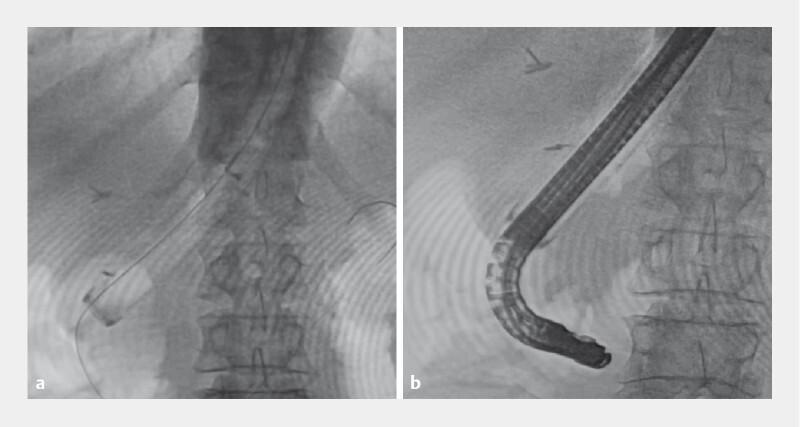

Sliding tube-assisted ERCP in a patient who underwent double tract reconstruction anatomy after proximal gastrectomy.

Endoscopy. 2023 Dec;55(S 01):E990-E992. doi: 10.1055/a-2145-1671. Epub 2023 Aug 21.

DOI:10.1055/a-2145-1671

PMID:37604450